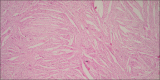

Histopathological examination is considered as gold standard procedure for arriving at a final diagnosis of various lesions of the human body. However, it is limited by a number of alterations of normal morphologic and cytological features that occur as a result of presence of artifacts. These artifacts may occur during surgical removal, fixation, tissue processing, embedding and microtomy and staining and mounting procedures. They can even lead to complete uselessness of the tissue. It is therefore essential to identify the commonly occurring artifacts during histopathological interpretations of tissue sections. This article reviews the common artifacts encountered during slide examination alongside the remedial measures which can be undertaken to differentiate between an artifact and tissue constituent.